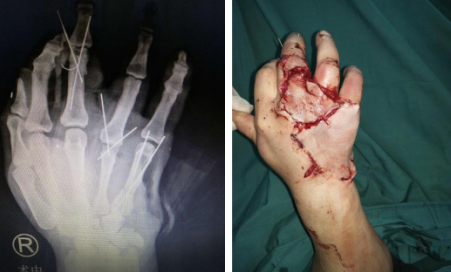

你看到下面这张图的第一感觉是什么?你觉得这只手还能救活吗?

2019年3月20日,徐州铜山区的村民李大同(化名)被120送至betway在线登陆。急诊大厅内,护士一边检查,一边电话通知手外三病区......据李大同妻子描述,丈夫在家中干活时不慎被拖拉机上的“三角带”绞伤,她当时吓得腿都软了。因为知道betway在线登陆的手外科很有名,他们便第一时间选择来sararz。

手外三陈步国主任接诊后,为患者做了专科检查,诊断其右手三指“旋转撕脱性离断”,再植手术难度很大。李大同的妻子哭着恳请陈主任一定救救自己的丈夫,哪怕只有万分之一成功的可能,他们也要手术。

断指再植手术有简单和复杂之分,切割伤较简单,断指成活率也高;而撕脱伤较难,尤其是多指撕脱性离断,不仅手术时间长、难度大,恢复起来慢,预后功能差。既然家属保指意愿强烈,陈主任手术团队决定为患者努力一搏。术中,进行清创,血管、神经、肌腱复位。术后半月,在手外三医护团队的悉心护理下,患者三根断指全部顺利成活。